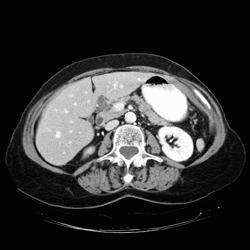

RADIOLOGY: PANCREAS: Case# 33079: AML & PANCREATIC MASS. This is an 83-year-old female complaining of one month of abdominal pain and hard stools. 1. Mass in the head of the pancreas, containing multiple cystic structures. This is most probably benign as it does not appear to invade adjacent structures and does not compress or obstruct the duct. This is probably a microcystic adenoma, without malignant potential. 2. Multiple splenic lesions. These are very small, and are indeterminate. They possibly represent hemangiomas, abscesses or cysts, but are unable to be determined by this exam. 3. Angiomyolipoma of the right kidney.4. Bartholins gland cyst.